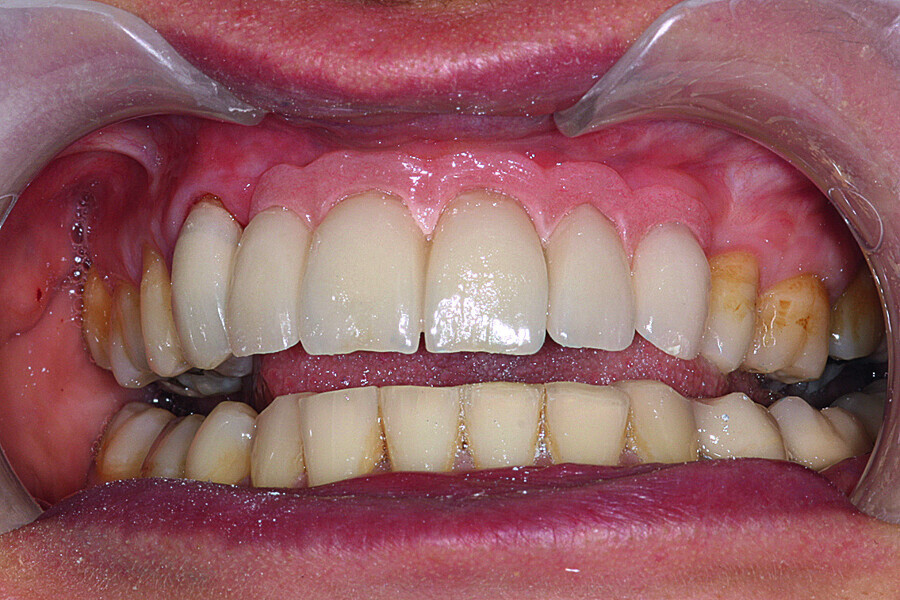

Fig. 38: Final cosmetic check-up showing correct lip support with the new extremely reduced false gingiva.

Fig. 39: Final cosmetic check-up showing correct lip support with the new extremely reduced false gingiva.